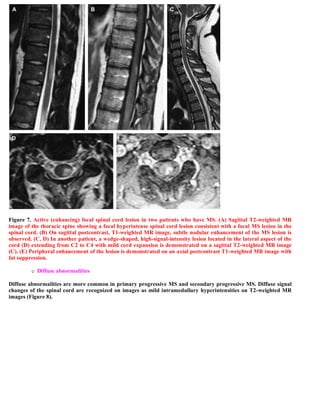

This document discusses a case of spinal multiple sclerosis in a 40-year-old patient. MRI images show well-defined pencil-shaped lesions occupying 2-3 spinal segments that are hypointense on T1-weighted images and hyperintense on T2-weighted images. Diffuse abnormalities are also seen as poorly demarcated hyperintense regions on T2-weighted images. The diagnosis is spinal multiple sclerosis. The document then discusses features of spinal MS lesions seen on MRI such as focal lesions, diffuse abnormalities, and spinal cord atrophy, and compares features of MS to other conditions like neuromyelitis optica.